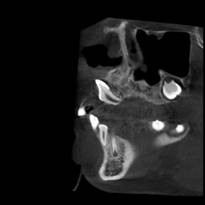

颅颌面CBCT

诊断范围涉及牙体牙髓病、牙周病、阻生牙/多生牙定位、种植牙术前CT评估分析、颞下颌关节CT诊断分析、,颌骨及涎腺疾病、颌面发育畸形、正畸治疗辅助诊断等大部分颌面部疾病,为临床医疗提供强有力的支持。